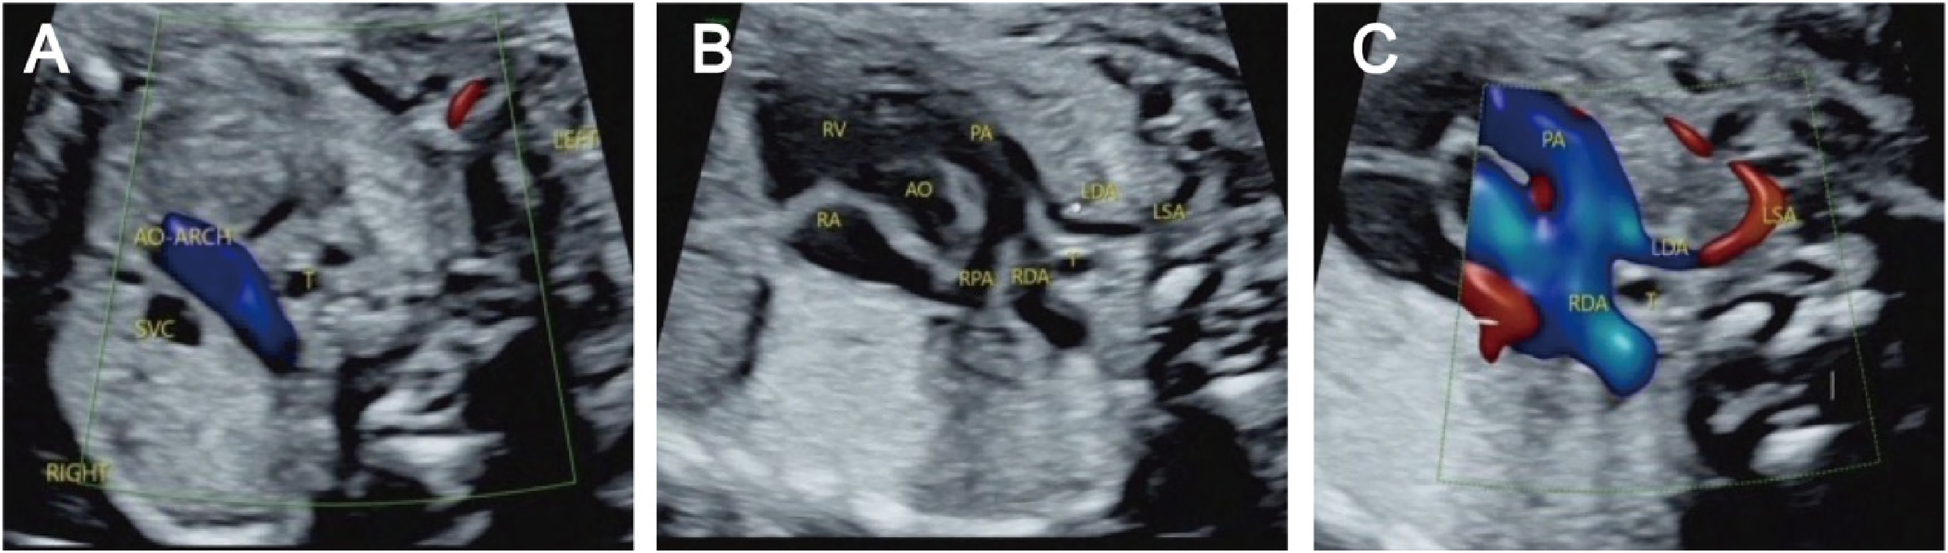

Figure 4

Right aortic arch with an isolated left subclavian artery and double ductus arteriosus. (A) Three-vessel and trachea view showing that the aortic arch is located on the right side of the trachea; (B/C) An arterial ductus is observed on each side of the trachea, the right arterial ductus is located on the right side of the trachea, and the left subclavian artery is connected to the aortopulmonary artery through the left ductus arteriosus.